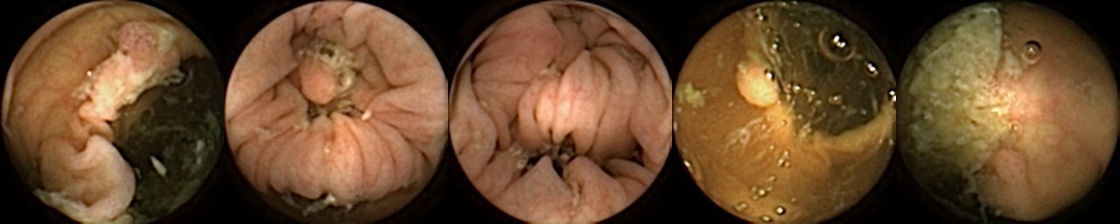

The data used in our study is based on the CareForColon2015 [kaalby2020colon, baatrup2025choice] trial conducted in the Danish colorectal cancer screening programme, which used the PillCam™ Colon 2 (Medtronic, USA) [Negreanu2013] camera capsule. We have access to 2,780 polyps from 853 patients from the CareForColon2015 study for which clinicians from the Department of Surgery of Odense University Hospital have exported up to five images per polyp. These five images correspond to 1) first partial, 2) first full, 3) best full, 4) last full, and 5) last partial image of the same polyp. This means that image 1 and 5 might just partially show the polyp. These are images from the same passing, so we know that there are no cases of the same polyp being seen at a significant later passage time. When we restrict the set to those polyps that the clinicians were able to export all these five images, we end up with 1912 polyps from 754 patients. These include 263 patients with one polyp, 204 patients with 2 polyps, 113 patients with 3 polyps, 77 patients with 4 polyps, and the rest with 5 or more polyps. Each set of five images from a polyp is given a unique patient ID and a unique polyp number.

Refer to caption

Figure 1: Positive exemplar images with each row showing five images of a unique polyp, where in each row, the first image corresponds to first partial and fifth image is the last full view of the same polyp. The polyps have been marked in green for each image.

For MIV, we construct both positive and negative exemplar pairs from this multi-patient polyp image dataset. Positive exemplars are constructed based on the five images from a single polyp, with one of the second, third, or fourth image designated as the query and the remaining four images forming the target bag. Images from five example polyps are shown in Figure 1. Negative exemplars are constructed using a more sophisticated strategy: if a patient has multiple polyps, the query image is selected from one of those polyps at random, while target images are sampled from other polyps of the same patient; if a patient has only one polyp, target images are drawn from different patients entirely.